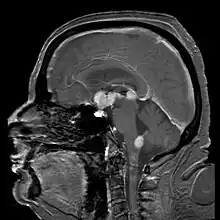

![]() Linfoma não Hodgkin | |